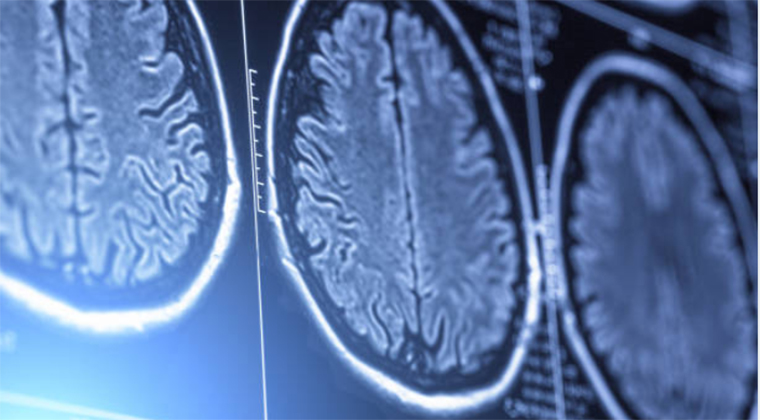

Laser Interstitial Thermal Therapy. This is another innovative way of surgery that uses heat and works by destroying the tumour via a small incision in the skull. With this procedure, the neurosurgeon inserts a tiny laser and directly targets the cancer cells. Heat is then transferred, destroying the tumour without harming the surrounding healthy tissues. Neurosurgeons like Dr. Timothy Steel use MRI visualization to monitor the patient’s brain. Real-time monitoring is practised to check if the brain’s area gets warm. When it does, doctors can reduce the heat to avoid damage.